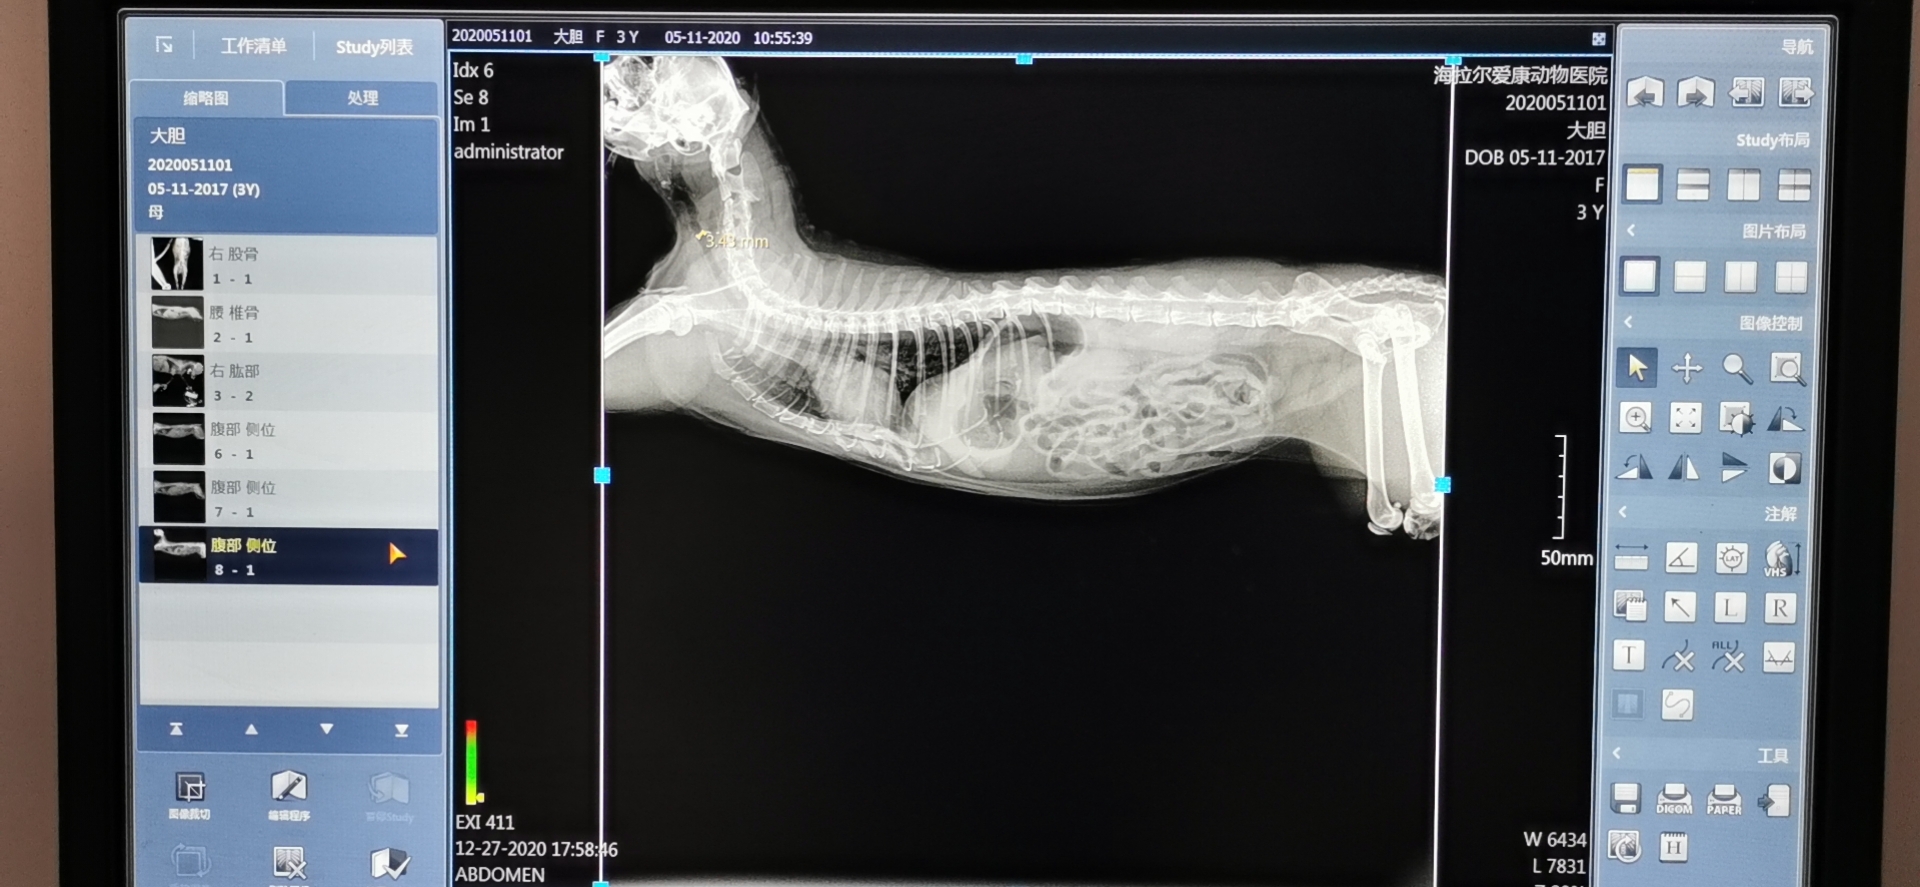

2)影像质量:高质量高稳定的成像质量是购置DR设备的初衷之一,也是提高诊疗水平的物理基础。其涉及放射影像的信噪比、分辩率、清晰度、对比度、细节显示等方面,主要由探测器技术、球管X射线质量、后处理功能、各硬件与计算机操作软件的兼容性决定。